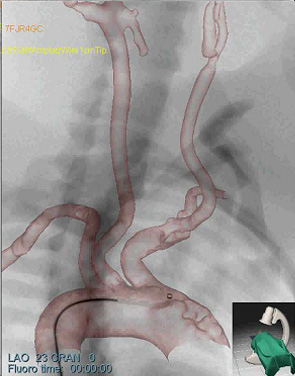

研究使用SimbionixANGO导师TM以色列dd站ANGO导师TM综合软件硬件内置模拟平台1a)模拟干扰程序基于诊断CTA和脉冲模拟模型支持实事求是插管操作反馈1b)并创建连续X射线成像、froscicC-arm定位和模拟反射剂注入2a-c)详情见http://www.simbionix.com

模拟模型直接转至SimbionixANGO导师TM模拟平台然后我们执行常用干预放射程序,如导管插入和操作、气球定位和放大,并插入病人专用模型微博2a-c显示样本快照模拟